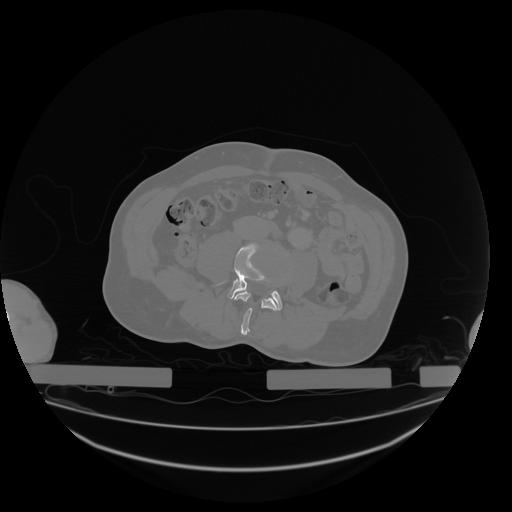

34 CUERPO,CE,Vol,1.0,CUERPO,,